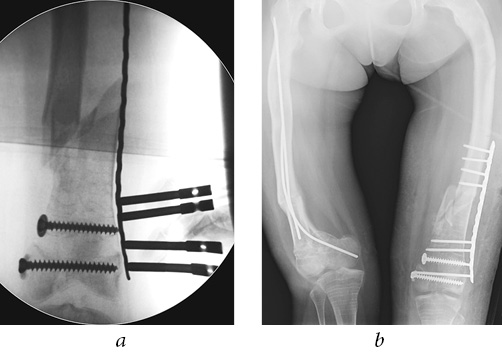

The first stage of the surgery was osteosynthesis of the distal metaepiphysis of left femur by two cannulated cancellous screws of 6.5 mm in diameter with full threading and with washers above and below the growth zone. Next, an attempt at retrograde osteosynthesis of TEN d = 3.0 mm was made from the standard approaches proximal to the growth zone. Due to the extremely low quality of the bone tissue and the comminuted nature of the fracture of metaphyseal zone, the titanium rods broke the cortical layer of the bone at the site of their insertion or perforated the opposite cortical layer (Fig. 4). It was decided to perform antegrade insertion of internal fixation devices. The rod was inserted through the lateral cortical layer of the upper third of femur and brought to the distal metaepiphysis, and then fixed in place with screws. Due to the small size of the distal metaepiphysis, in order to ensure satisfactory fixation, we perforated the growth zone. The distal end of the rod was placed behind the proximal screw and in front of the distal screw before being fixed in the subchondral zone of bone. Osteosynthesis with a second rod was not possible due to the narrow intramedullary canal. Enlarging the canal by drilling was technically impossible without additional surgical access, which would have significantly increased blood loss, volume, and time of surgery (Fig. 5 a).

Fig. 4. Intraoperative radiograph, TEN perforation of the opposite cortical bone layer

After the end of immobilization of the left lower extremity, the patient complained of a persistent restriction of movement in the left knee joint. After 2 months, control radiographs revealed TEN migration to the proximal tibial metaepiphysis (Fig. 7), which caused the blockade of the knee joint and indicated the need for a repeated surgical intervention. The patient complained of pain in the medial regions of the right knee joint during movements. The absolute stability provided by the cancellous screws in the area of the splitting of the left femoral condyles created the conditions for complete consolidation of fracture and an absence of secondary displacement. The fracture of the right femur was also consolidated.

Fig. 7. Radiographs of the left femur: a — frontal view; b — lateral view: migration of TEN into the proximal tibial epiphysial cartilage, delayed consolidation